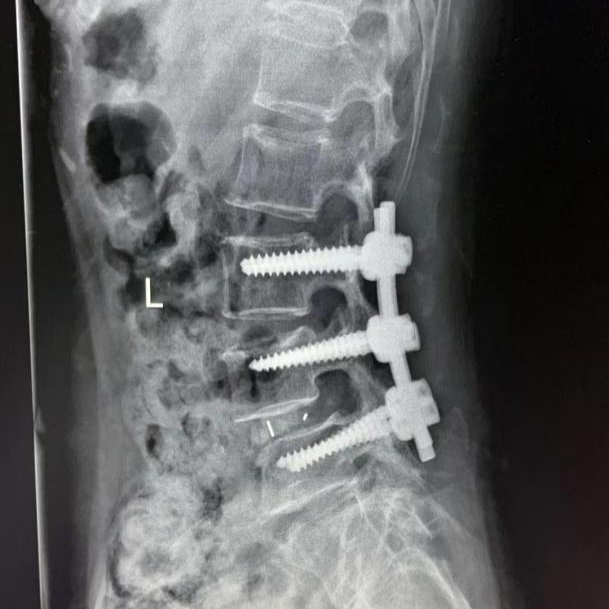

患者王婆婆已經(jīng)71歲了,近13年來反復(fù)腰部伴雙下肢疼痛無力,保守治療無效,近期尤為明顯,行走幾百米就小腿脹痛明顯,無法繼續(xù)走路,嚴(yán)重影響日常生活。加之子女遠(yuǎn)在國外,無法照顧王婆婆,她輾轉(zhuǎn)多個(gè)三甲醫(yī)院,最后選擇轄區(qū)較近的我院外科入住。入院后外科積極進(jìn)行圍手術(shù)期管理,醫(yī)患溝通,嚴(yán)格落實(shí)核心制度。完善相關(guān)檢查,診斷為腰4椎體骨折并滑脫、椎管狹窄。外科結(jié)合術(shù)前的各項(xiàng)檢查,細(xì)致的術(shù)前討論,制定了合理的手術(shù)方案,最終決定為患者實(shí)施“腰3-5置入椎弓根螺釘,腰4-5椎板切除減壓椎間植骨融合復(fù)位釘棒內(nèi)固定術(shù)”,歷經(jīng)3小時(shí),手術(shù)順利完成,術(shù)中出血僅300ml,,術(shù)后患者雙下肢感覺運(yùn)動(dòng)正常,腰腿疼痛立即緩解?;颊邔?duì)治療效果非常滿意。術(shù)后第3天已經(jīng)下床行走,春節(jié)前即將順利出院,過一個(gè)真正快樂、毫無病痛的春節(jié)!

腰椎后路滑脫椎管減壓植骨融合內(nèi)固定術(shù)是脊柱外科常用的手術(shù)方式之一,其手術(shù)方法主要是經(jīng)腰椎后路打開椎管,松解粘連、緊張的神經(jīng)組織,切除病變突出的腰椎間盤,并植入椎間融合器及內(nèi)固定裝置,從而達(dá)到解除神經(jīng)壓迫,緩解腰椎間盤壓力,重建脊柱穩(wěn)定,降低患者復(fù)發(fā)率的目的。適用于腰椎間盤突出癥導(dǎo)致的腰腿部麻木、疼痛等不適,或腰椎間盤突出癥病情反復(fù)發(fā)作或者久治不愈,以及存在腰椎節(jié)段性不穩(wěn)導(dǎo)致的腰椎滑脫、腰椎管狹窄癥、脊柱側(cè)彎畸形、馬尾神經(jīng)疼痛等腰椎疾病。